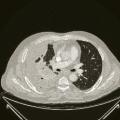

Voici ci-contre, afin d’illustrer l’importance à accorder à la recherche et la découverte de mutations d’intérêt thérapeutique, le cas d’un homme de 51 ans, non-fumeur, chez qui l’on découvre un adénocarcinome bronchique stade IV avec envahissement pleural et ganglionnaire majeur. Lafigure 1 correspond à son imagerie thoracique avant traitement, la figure 2 à son imagerie de réévaluation après traitement par un TKI de première génération ciblant sa mutation activatrice de l’EGFR.•

Voici ci-contre, afin d’illustrer l’importance à accorder à la recherche et la découverte de mutations d’intérêt thérapeutique, le cas d’un homme de 51 ans, non-fumeur, chez qui l’on découvre un adénocarcinome bronchique stade IV avec envahissement pleural et ganglionnaire majeur. La